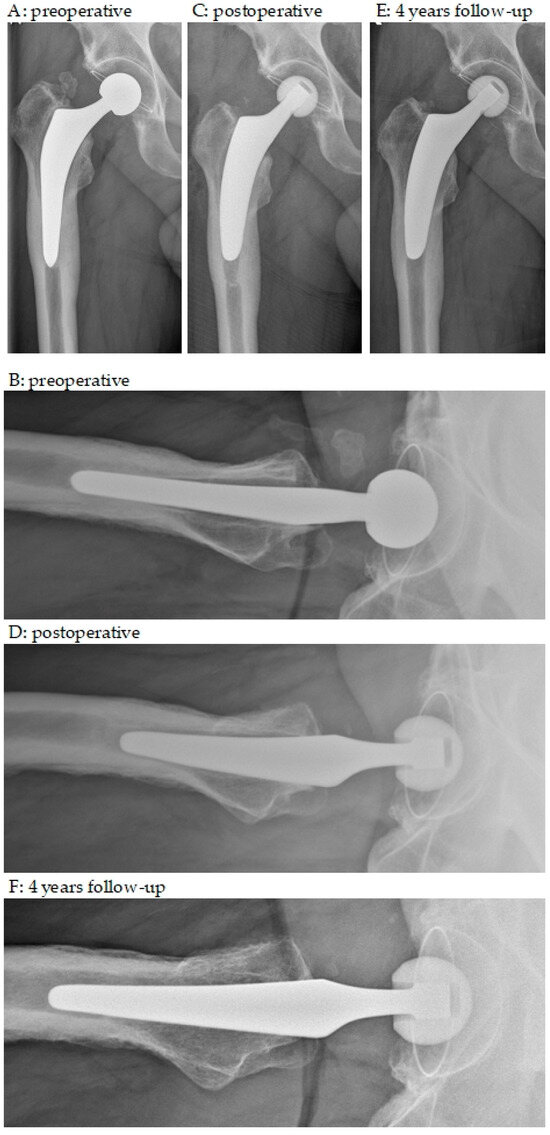

| Stem fixation | |

| stable | 24 (100%) |

| Stem subsidence | |

| <10 mm | 1 (4%) |

| ≥10 mm | 1 (4%) |